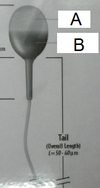

[Neutrophils]

A) Which is the mature form?

B) Which is the immature form?

A) B

B) A